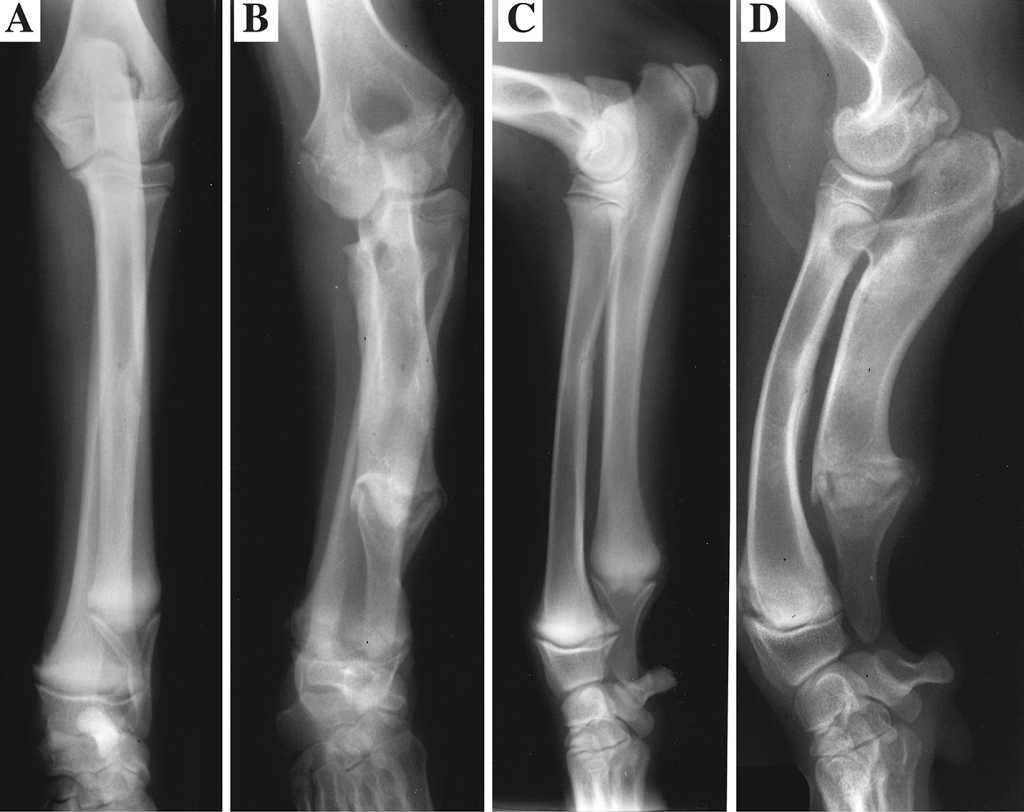

Exámenes radiológicos e histopatológicos exhaustivos realizados en aquel momento revelaron graves deformidades en las extremidades, incluyendo radios y cúbitos acortados, placas de crecimiento irregulares y osificación endocondral alterada.